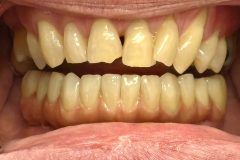

Implant Work by Dr Kevin Bruce:

Full smile rehabilitation involving replacement of missing and failing teeth with implant-supported restorations, combined with aesthetic correction of existing dentition. The treatment was carefully planned to restore function, improve alignment, and achieve a balanced, natural-looking smile.

Implants were strategically placed to support long-term stability, with particular attention to soft tissue contours and emergence profiles to ensure seamless integration with the surrounding teeth. The final restoration was designed to enhance both aesthetics and bite function, delivering a confident and harmonious result.

This case demonstrates a comprehensive approach to implant and restorative dentistry, combining surgical precision with advanced prosthetic design to achieve predictable, long-term outcomes.